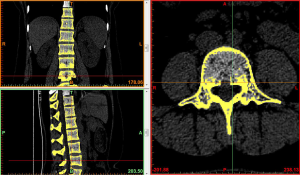

Image import: 392 horizontal images of the thoracolumbar spine in DICOM format were imported into Mimics 15.0 medical image processing software, which automatically located the images and displayed them according to the three orthogonal planes (coronal, horizontal, and sagittal), respectively (Figure 2).

Threshold segmentation: it was easy to distinguish the bones from the soft tissues based on the obvious differences in their CT values on the CT images by using the threshold segmentation method, and a mask was formed. If the gray values of adjacent pixels were close to each other and it was not easy to distinguish the boundary by the naked eye, the Draw Profile Line and the Thresholding functions in Mimics 15.0 medical image processing software were used to adjust the image threshold to 462–2,676 HU, so that the boundaries of the thoracolumbar vertebral body, intervertebral disc, sacrum, and facet joint were clearer (Figure 3).